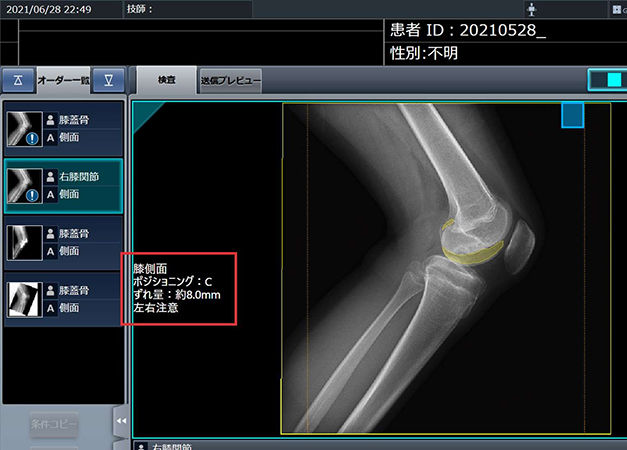

FPT와 코니카미놀타는 인공지능을 활용한 의료영상 진단 분야의 X선 영상의 동적 분석 등 공동 연구를 추진한다. NIC는 규제기관을 비롯해 의료기관과 협력해 법적 토대를 마련하고, 적합한 연구 환경을 조성하기로 했다.